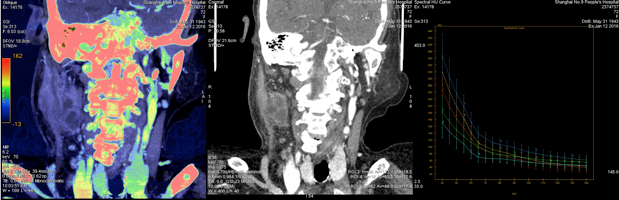

病例资料:女,72岁,颈部肿胀就诊 扫描方案:GSI22, 375mA@0.7s/rot@0.984:1@SFOV Large body 对比剂注射方案:300 mgI/100ml,对比剂60ml,盐水30ml,流速3.0ml/s CT印象:右侧颈部间隙感染 能谱分析:

能谱曲线:区分物质。黄色曲线代表间隙感染,与蓝色咀嚼肌曲线斜率明显不同,受感染侵犯的脂肪间隙的粉色曲线平直,与正常表达的红色反向走形的脂肪曲线明显不同 散点图:间隙感染、肌肉、脂肪组织均成相对独立集中的表达趋势

颈部间隙多发肿大淋巴结,能谱曲线表达高度相似,提示性质相同——炎性感染

小结: 1、CNR(最佳对比信号噪声比):可以准确把握颈部软组织病变的最佳单能成像; 2、能谱曲线:有助于颈部不同软组织之间性质差异的鉴别; 3、碘-水基物质分析:可对病变进行准确定量分析,同时还有助于疗效评估。 备注:该病例来自上海市第九人民医院